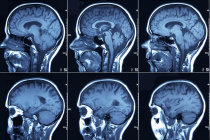

O diagnóstico20 de hipertensão1 intracraniana idiopática2 deve partir de dados da história clínica e do exame físico. Para confirmar o diagnóstico20 e para excluir outras causas concorrentes, diversas investigações laboratoriais e de imagens se fazem necessárias. Na pressão intracraniana idiopática2, esses exames podem parecer normais, embora vistos com atenção, os ventrículos estão apequenados e em forma de fenda e há dilatação das bainhas do nervo óptico e achatamento21 da glândula22 pituitária, devido ao aumento da pressão.

Tomografia computadorizada23 ou ressonância magnética24 podem ser usadas para excluir quaisquer lesões25 de massa. Uma venografia feita com o auxílio da ressonância magnética24 deve ser realizada para excluir a possibilidade de estenose26/obstrução do seio27 venoso ou trombose28 do seio27 venoso cerebral.